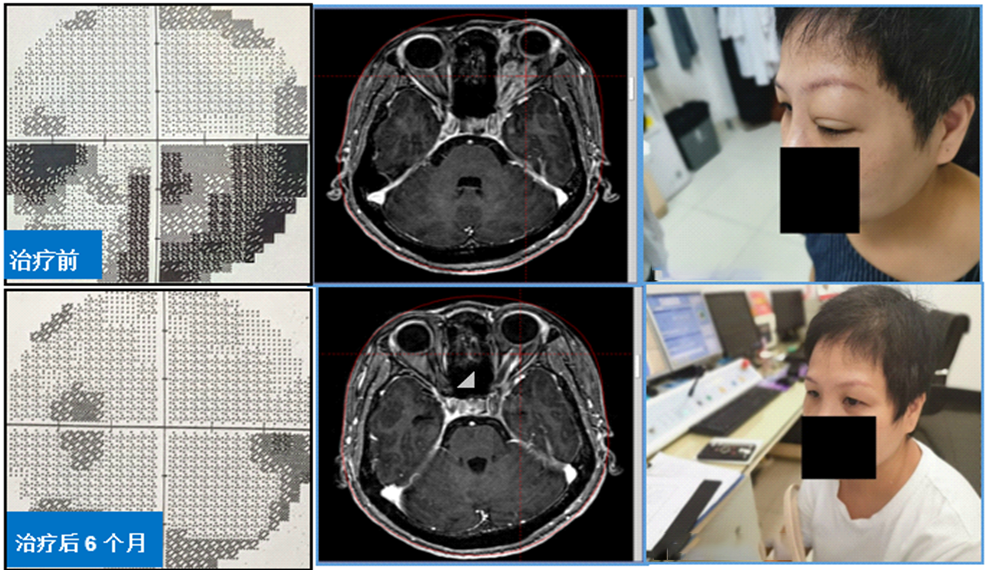

3、伽玛刀治疗眶内球后占位,保全视力视野、改善突眼症状。球后占位患者常伴有突眼、视力下降及视野缺损,伽玛刀分割治疗可快速缓解突眼症状,减轻视神经压迫,再逐步“吃掉”残余肿瘤。该方法是眶内球后占位最有效的治疗手段之一。